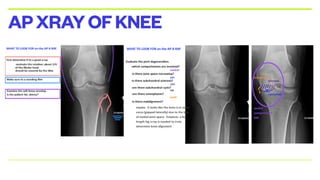

• STANDING XRAY OF KNEE AP AND LATERAL VIEW

APXRAYOFKNEE